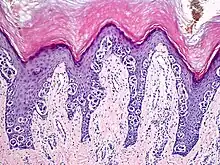

An acral nevus is a cutaneous condition of the palms, soles, fingers, or toes (peripheral body parts), characterized by a skin lesion that is usually macular or only slightly elevated, and may display a uniform brown or dark brown color, often with linear striations.[1]: 1726

Acral nevi may occur in all ethnic groups, but are more common in dark-skinned people. The acral nevus is a benign skin lesion that can occur at any age, but is generally noticed between 10 and 30 years of age. Both children and adults may be observed with this skin lesion. The prevalence of acral nevi increases directly with degree of skin pigmentation. In a study, palmar or plantar nevi were detected in 42.0% of black (50 of 119) vs 23.0% of whites (79 of 343). Palmar or plantar nevi of 6 mm diameter or larger were detected in 3.4% of blacks (4 of 119) vs 0.6% of whites.[2]

They are brown to dark brown in color and have linear streaks of darker pigmentation. Size is usually 7 mm or less, oval or spindle shaped, and well-demarcated. They become stable after an initial growth phase, and the number of lesions also decreases; a new lesion in middle-aged or elderly people should raise suspicion of acral lentiginous melanoma.